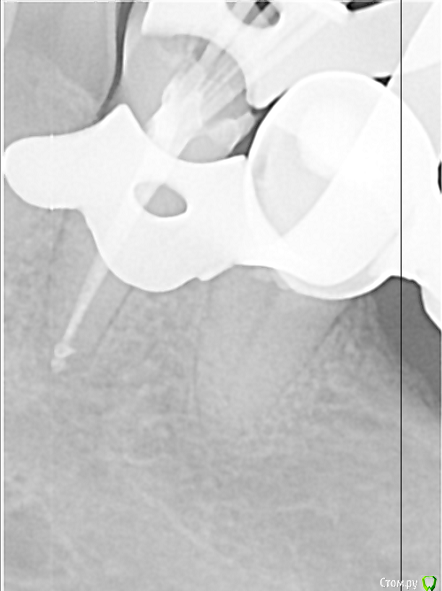

По закону парных случаев с интервалом в неделю приходит обострение хронического периодонтита 15 с каналонаполнителем в вестибулярном канале. Стандартная обработка. На обтурации долго возился с определением рабочей длинны и видимо получилось так себе... Аверон не тащит, да и снимок не всегда объективен. Коплю на Морита Root ZX Mini)))